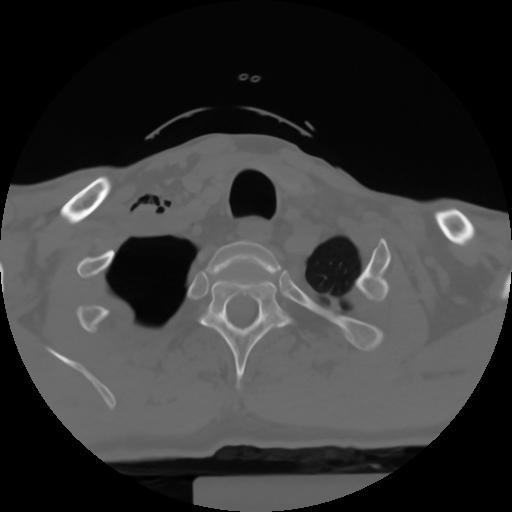

10 P.BLANDAS,,Axial,2.0,P.BLANDAS,,